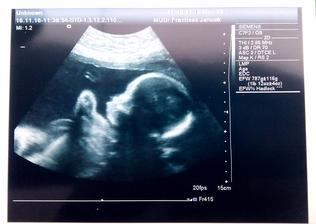

Dozvedela som sa to v júni keď mi tri dni pred ms začala rozprávať moja dcérka že mám v brušku bábätko. Tak som si urobila test až jeden deň pred tým ako mala prísť mrcha a zrazu dve čiarky. Tak sme sa hrozne tešili. Mysleli sme že termín bude marcový keďže v máji som mala ešte ms ale tak sme zistili že aj keď bola v máji mrcha tak už som bola tehu. Darmo máj lásky čas. Pohlavie sme sa dozvedeli v 16tt a druhý a posledný krát ho bolo vidieť 20tt. Od vtedy ssa schováva aj tváričku aj medzinozie 3D mi dr robil za každým na azdej poradni no ani jeden záber nič je to zrejme hanblivé bábätko . Tešíme sa už na neho budeme komplet